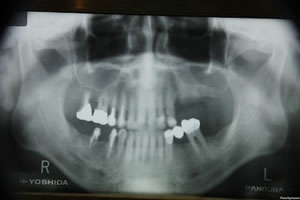

どこを手術するのかといえば、次のレントゲンの向かって左の上の奥歯の部分。ここは3ヶ月前に抜歯をしてもらいインプラントの準備をしたところ。

骨の厚みがどれくらいあるかが問題、私の場合は上顎洞(副鼻腔)との間だの距離がインプラント出来るギリギリのところだったようだ、この骨の厚さがたりないと、インプラントを埋め込む余裕がないということになる。